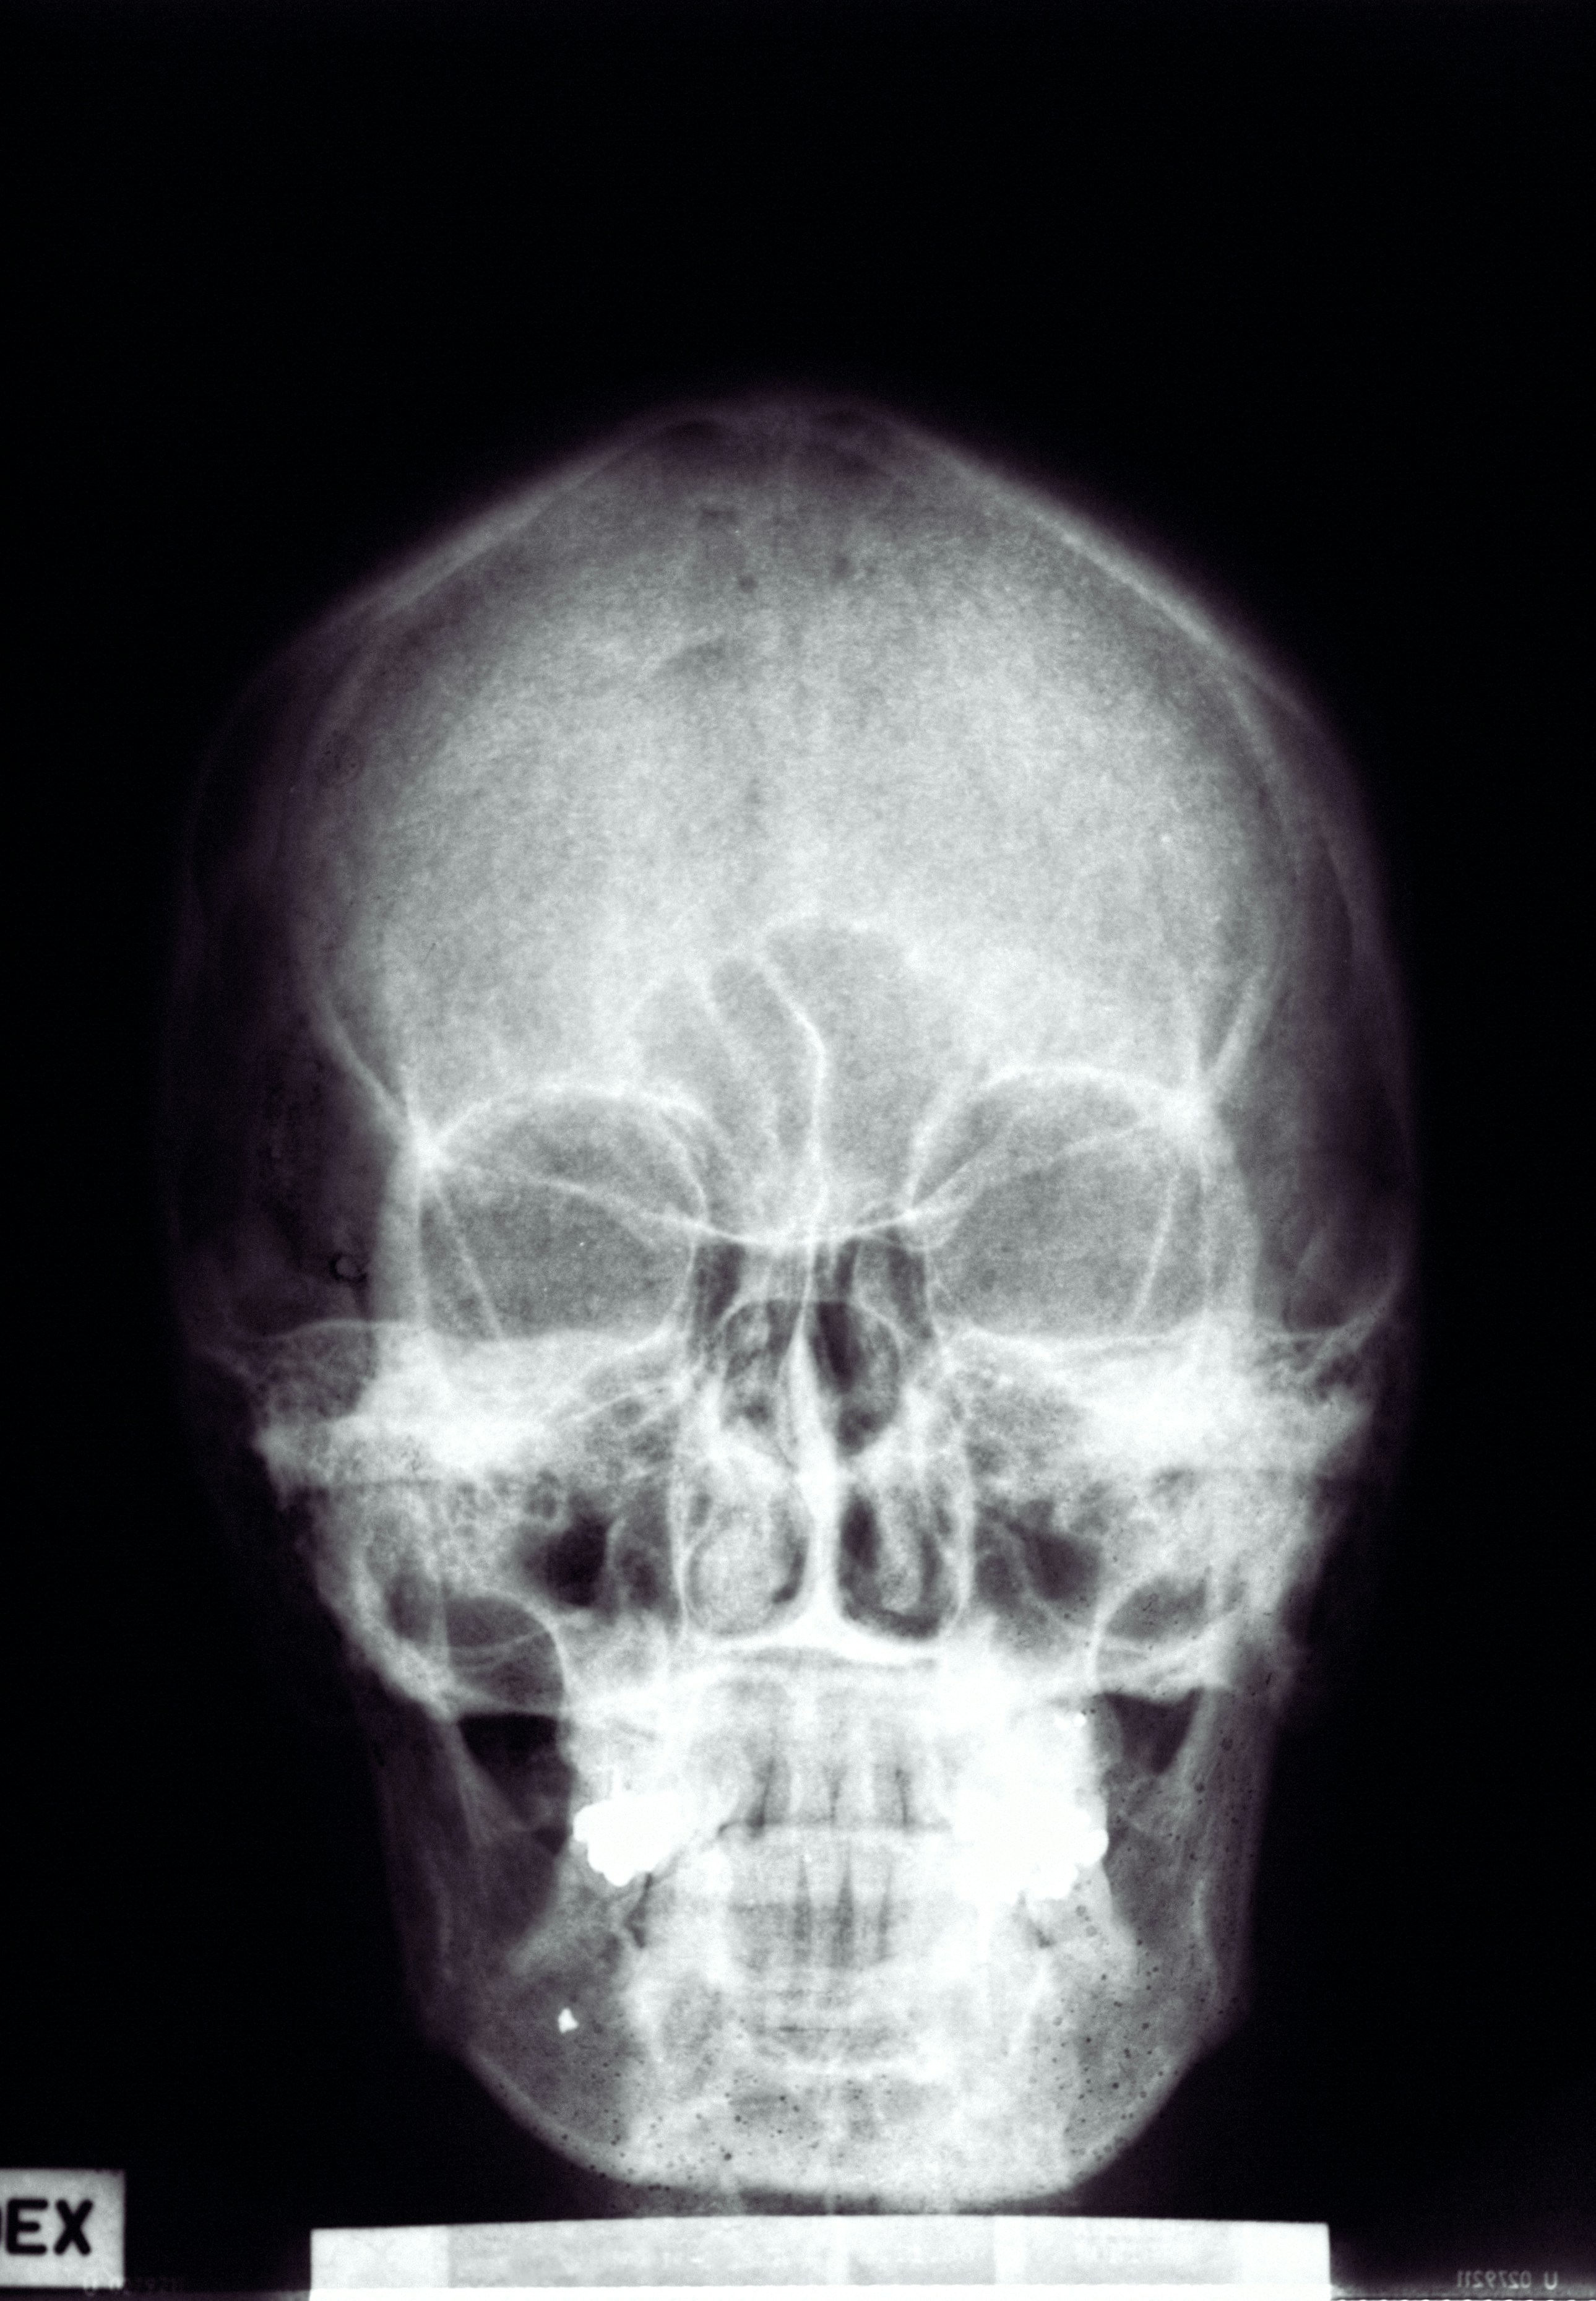

W trakcie badania technik radiologii ustawia głowę pacjenta w odpowiedniej pozycji, zależnie od tego, które zatoki mają zostać uwidocznione. Najczęściej wykonywane są zdjęcia w projekcji Watersa (potyliczno-bródkowej), która pozwala ocenić zatoki szczękowe i sitowie przednie, oraz w projekcji Caldwella (potyliczno-czołowej) dla zatok czołowych i sitowia tylnego. Dodatkowo możliwe jest wykonanie zdjęć bocznych lub w projekcji podstawy czaszki, co umożliwia kompleksową ocenę wszystkich grup zatok przynosowych. Samo wykonanie zdjęcia trwa zaledwie kilka sekund, a cała procedura – od wejścia do pracowni do jej opuszczenia – zazwyczaj nie przekracza kilku minut.

Obrazowanie zatok przynosowych za pomocą promieniowania rentgenowskiego umożliwia wykrycie wielu istotnych zmian patologicznych. Na zdjęciu RTG można uwidocznić obecność płynu w zatokach, co często świadczy o stanie zapalnym lub infekcji. Badanie pozwala również zidentyfikować polipy zatokowe, czyli łagodne rozrosty błony śluzowej, które mogą prowadzić do przewlekłej niedrożności nosa i nawracających infekcji. Oceniany jest także stopień upowietrznienia zatok, co ma znaczenie przy podejrzeniu przewlekłych procesów zapalnych lub zmian anatomicznych utrudniających prawidłową wentylację tych struktur.

RTG zatok znajduje zastosowanie w diagnostyce urazów – umożliwia wykrycie złamań kości otaczających zatoki, takich jak kość nosowa, jarzmowa czy ściany zatok szczękowych. Jednak należy pamiętać, że klasyczne prześwietlenie nie zawsze pozwala na precyzyjne określenie rozległości zmian, zwłaszcza w przypadku niewielkich złamań lub skomplikowanych urazów. W takich sytuacjach lekarz może zdecydować o skierowaniu pacjenta na tomografię komputerową (CT), która zapewnia znacznie wyższą czułość i szczegółowość obrazu.